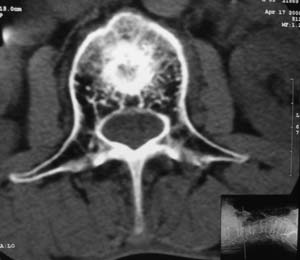

以下是引用余辉在2008-4-27 17:12:00的发言:[br]骨质疏松伴病理性压缩性骨折,椎骨骨松质密度减低,椎体骨小梁稀疏且普遍呈火柴头样改变,椎体无膨胀,无软组织肿块

以下是引用mzh123在2008-4-27 19:33:00的发言:[br]除压缩骨折表现外 还有许莫氏结节改变

以下是引用随光逐影在2008-4-27 21:29:00的发言:[br]除压缩性骨折外,还有许莫氏结节及骨质疏松表现。